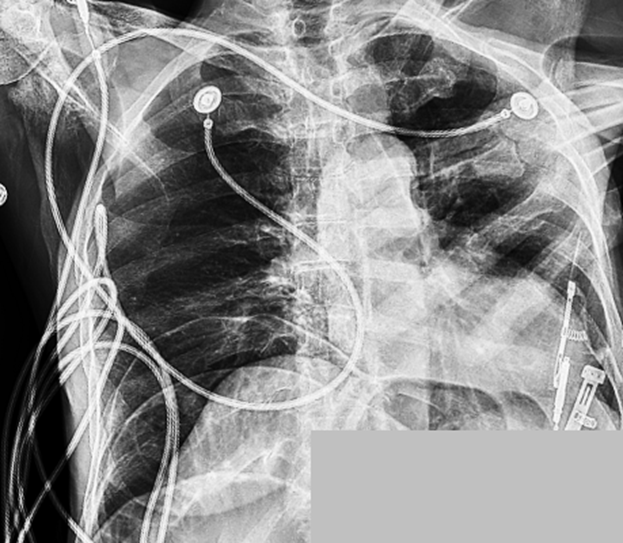

1. A 72-year-old female presented with altered mental status.

2. Physical examination revealed significant abdominal rigidity and rebound tenderness.

3. Arterial blood gas analysis demonstrated an elevated lactate level of 3.8 mmol/L (reference range: 0.5–1.6 mmol/L).

4. Chart review showed no recent history of surgical procedures.

5. The image below is a portable chest radiograph.

• Chest Radiograph:

Large-volume pneumoperitoneum. Reduced lung volumes with associated bibasilar atelectasis.